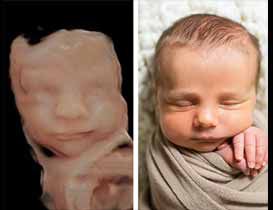

Obstetrics and gynecology: 3D ultrasound is commonly used in obstetrics to visualize the fetus and assess fetal growth and development. It can also be used to diagnose chromosomal abnormalities and congenital defects. In gynecology, it can be used to evaluate the uterus and ovaries, as well as to guide biopsy procedures.